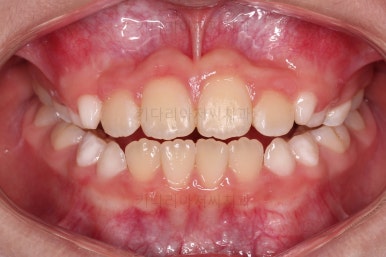

치료 종료!

총 13개월 걸려서 부산초등학생교정 위턱의 3차원적 성장과 앞니 가지런함을 다 이뤘어요.

앞니의 반대교합 뿐만 아니라 어금니 반대교합도 개선되었네요.